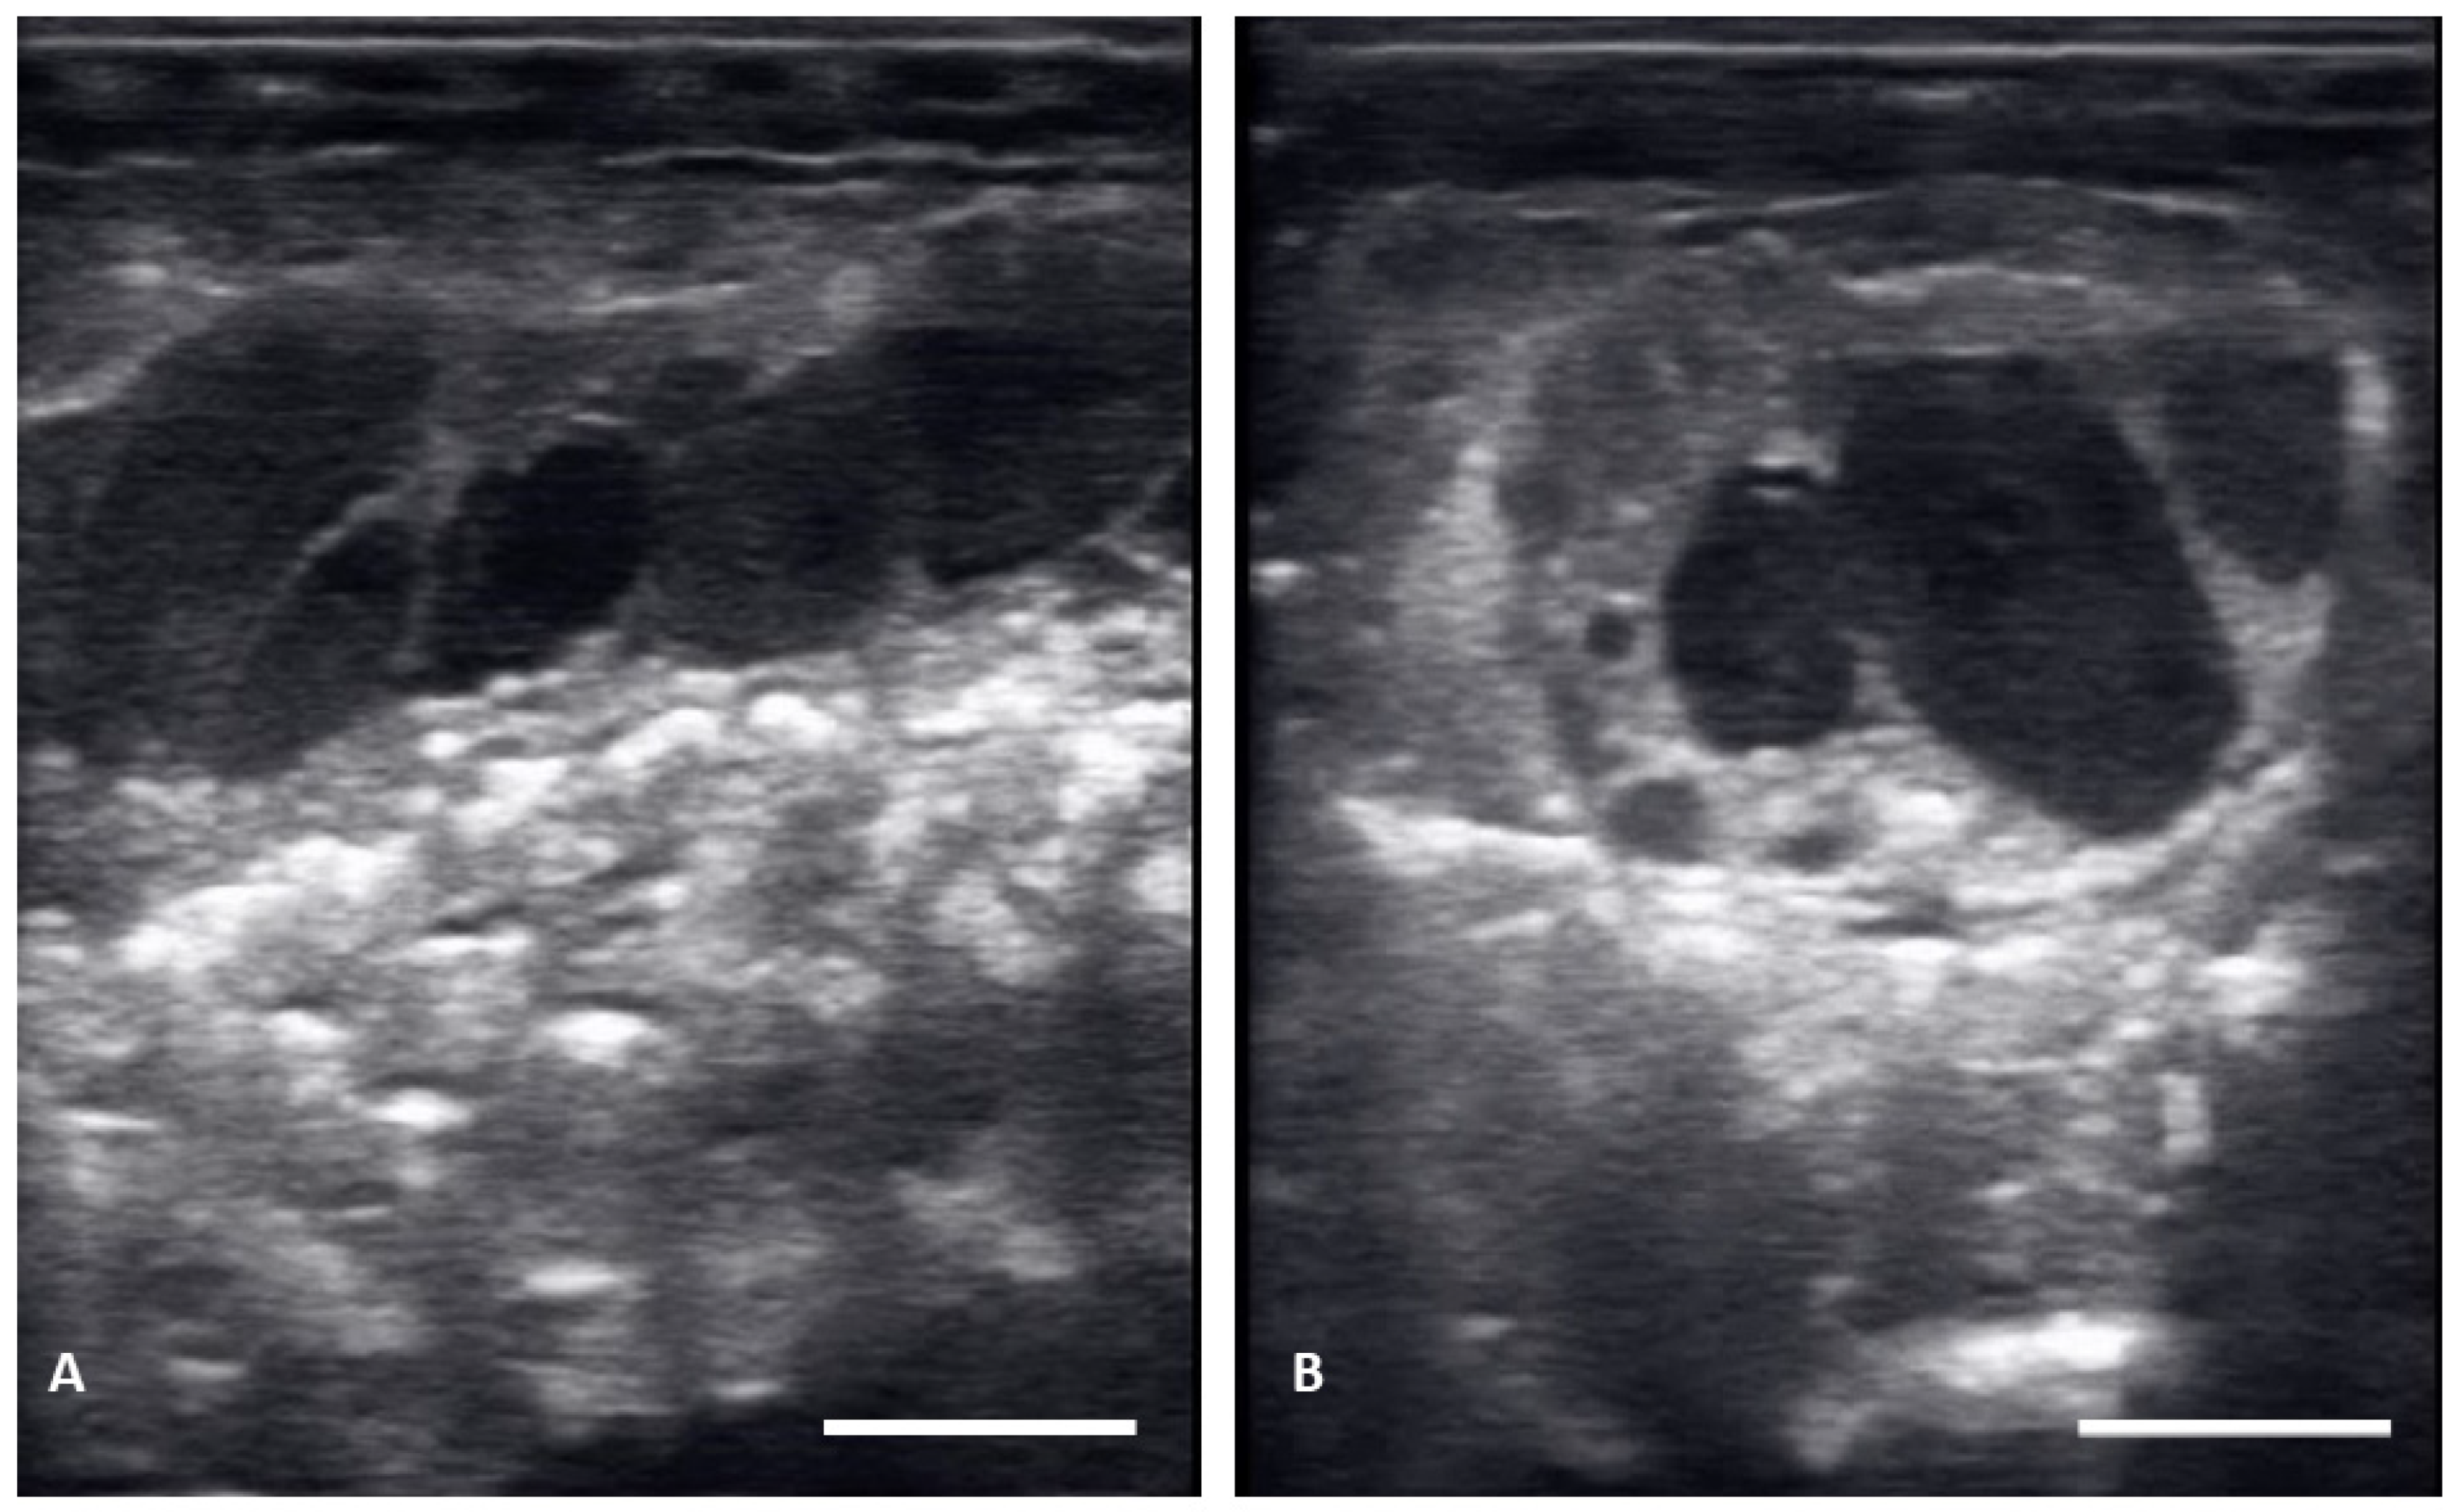

| Vitellogenic follicles (VF) | Oval shaped follicles showing a thickening hyperechoic outline as granulosa cell layer increase, hyperechoic ooplasm, and an anechoic core centrally located. |

| Preovulatory follicles (PrOV) | Elongating and increasing hyperechoic ooplasm as follicles are filled with yolk, with an elongated anechoic area located in the periphery of the ooplasm. |